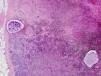

El caso de un paciente que se sometió a una linfadenectomía dos semanas después de haberse realizado una EBUS-TBNA. La biopsia de un ganglio paratraqueal inferior demostró la presencia de pigmento antracótico en los macrófagos y de dos fragmentos de cartílago en su interior, tal como muestra la imagen anatomopatológica.